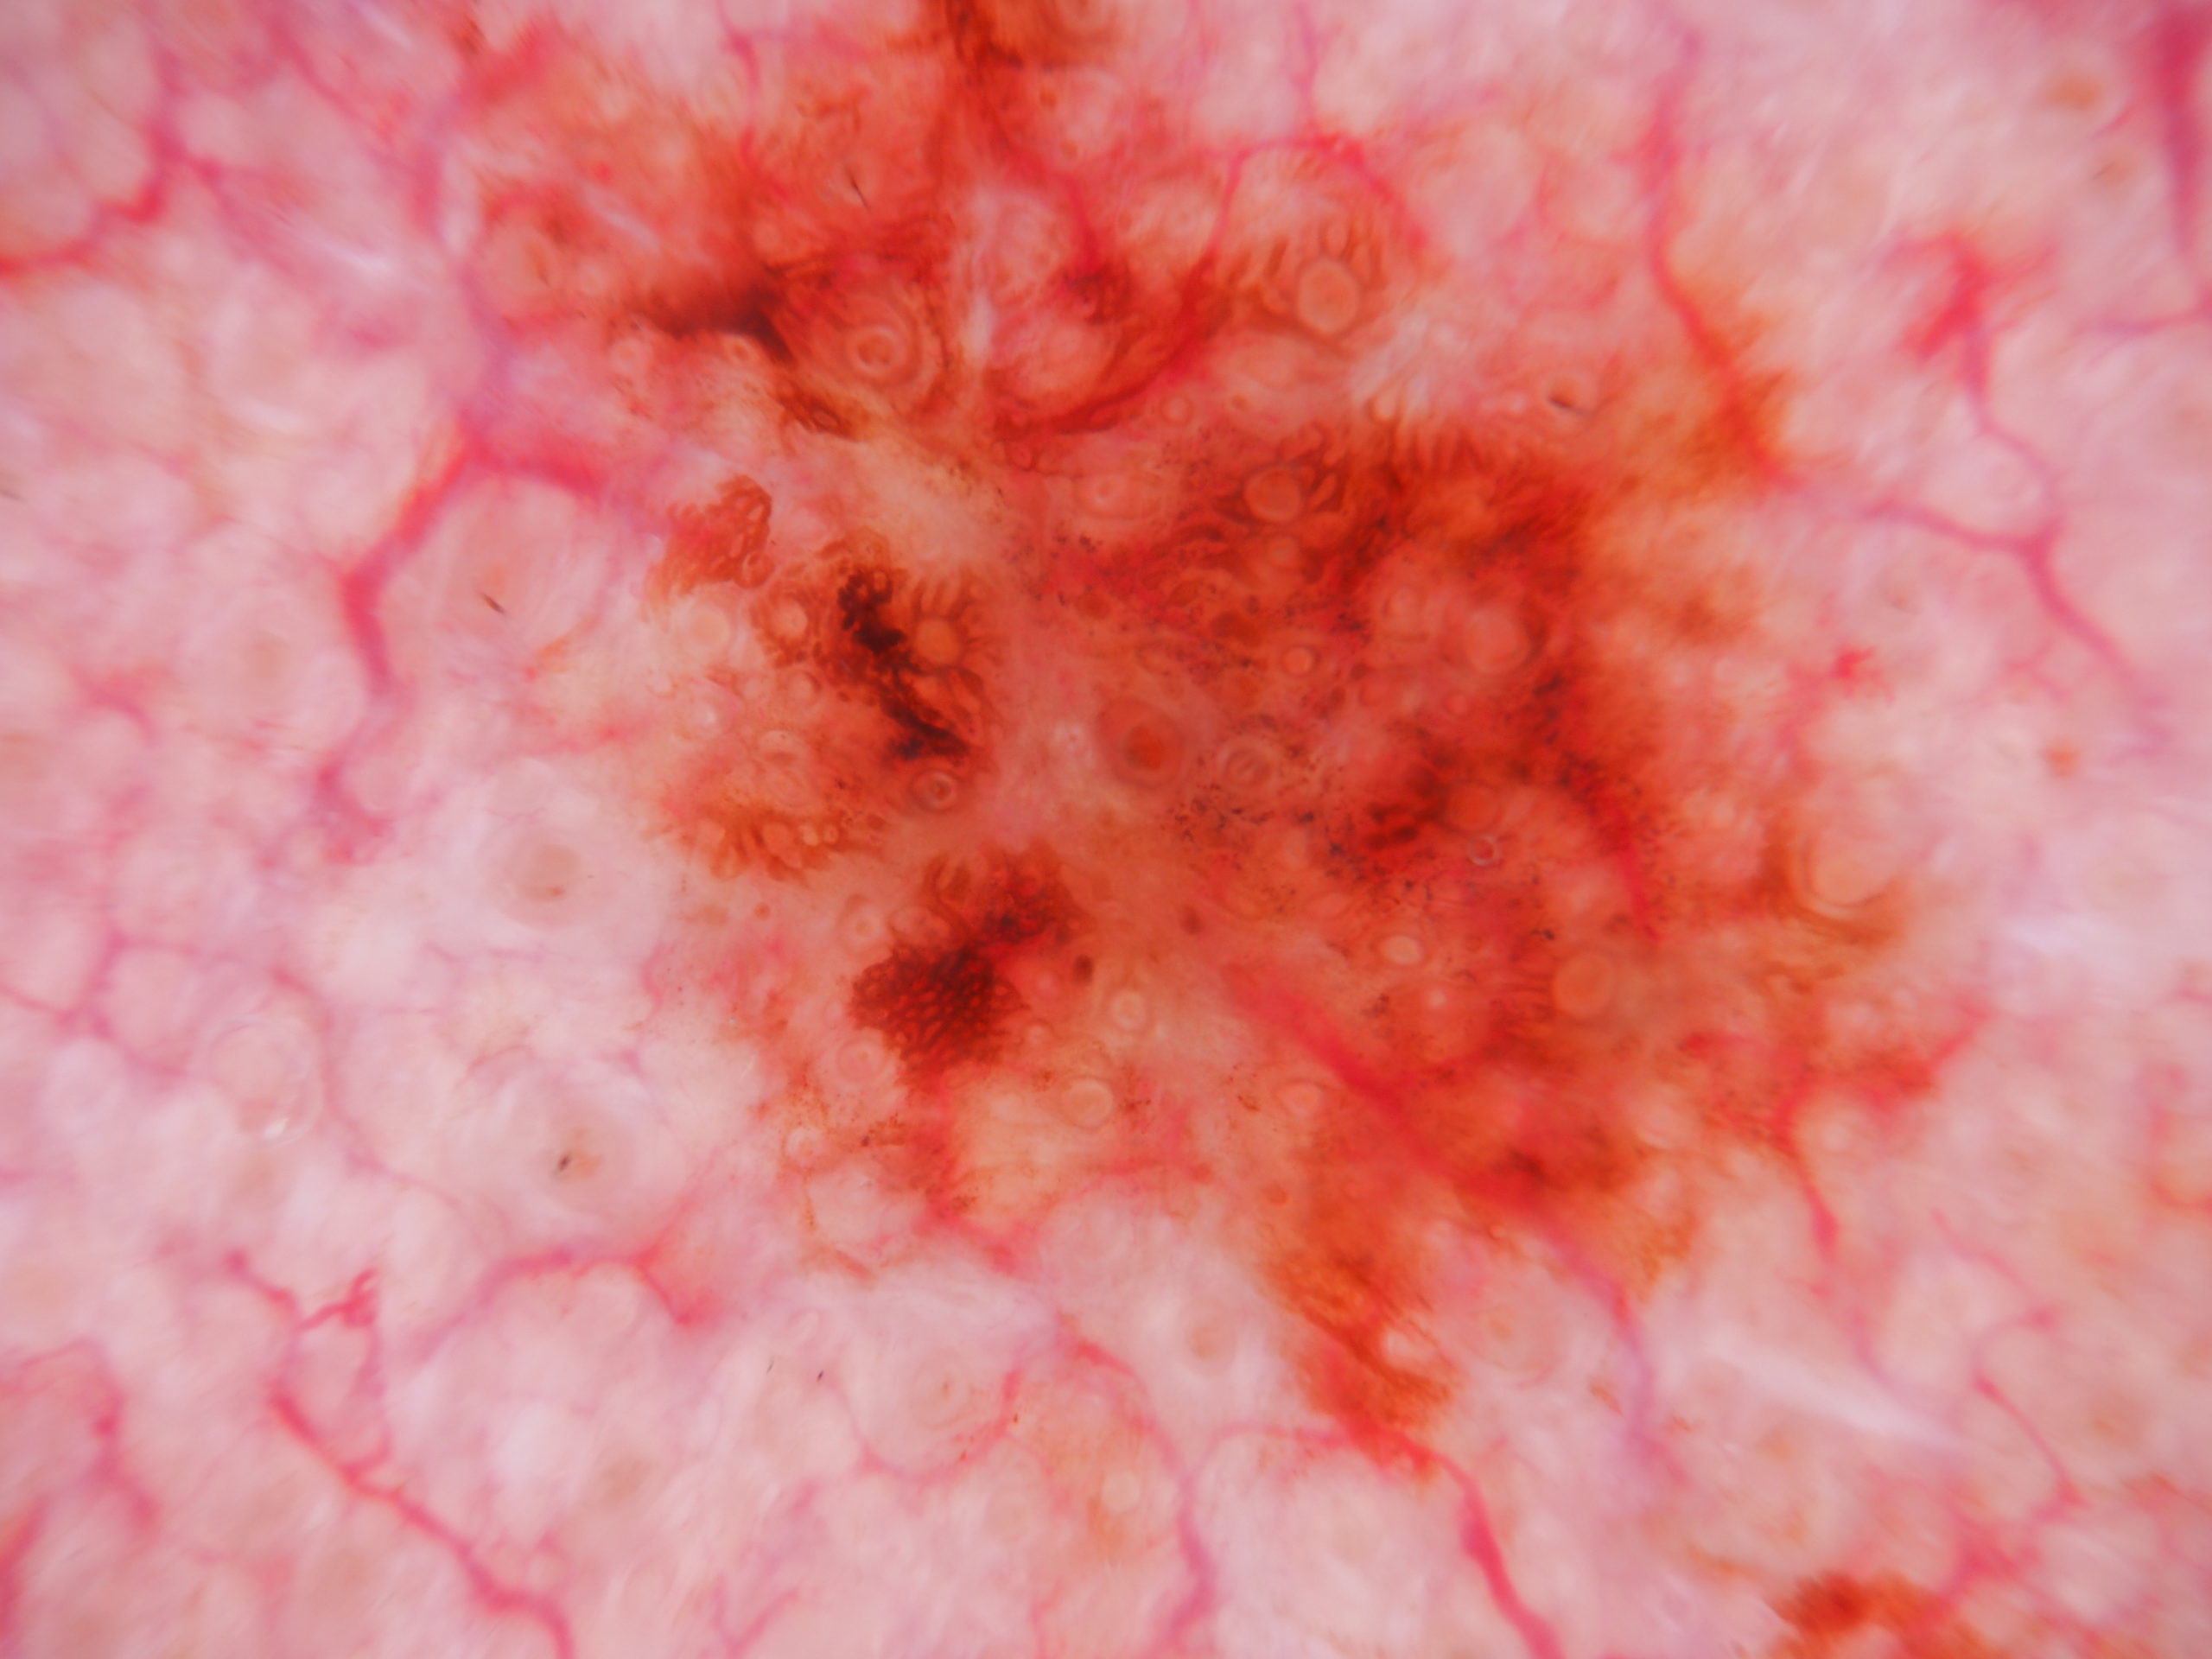

Image Number #3803 (Lentigo Maligna)

Site: Cheek

Diagnosis: Lentigo Maligna

Sex: M

Age: 65

Type: Dermlite Polarised

Description: Slowly growing pigmented lesion cheek

A pigmented lesion on the cheek that has slowly been increasing in size over several years. Male aged 65. Smooth surface.

Dermatoscopy shows pigment dots and pigment around follicles as grey circles. PRAME and Sox 10 showed atypical melanocytes along the DEJ extending into and down follicles with localised upward pagetoid spread. Early Lentigo maligna / Superficial intraepidermal melanoma.